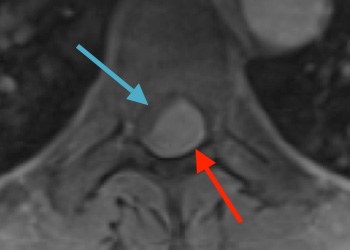

Spine:

Cervical Laminectomy and Fusion

Author: William Sonstein M.D., F.A.C.S., Read More!

Thoracic Spinal Cord Tumor Case Presentation

Author: Xavier P. J. Gaudin D.O., F.A.C.O.S., Read More!